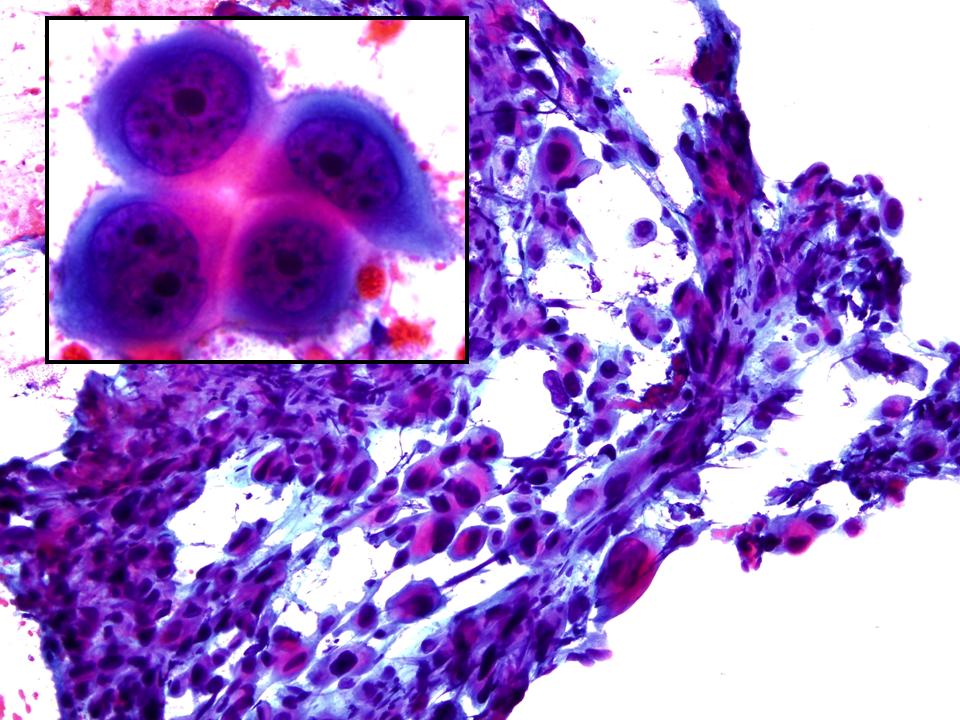

Dr. Ignacio Guasch, Dr. Edwin Mejía.

Hospital Germans Trias i Pujol, Badalona.

Hombre de 59 años, bronquítico crónico que refiere aumento del volumen mamario bilateral. Con una TC que informa masa tumoral en mediastino medio, voluminosa, sólido- quística, con extensa necrosis tumoral y adenopatías mediastínicas paratraqueales de tamaño significativo. Se realizar una PAAF guiada Ultrasonografía Ecobroncoscópica (EBUS) para el diagnóstico definitivo.